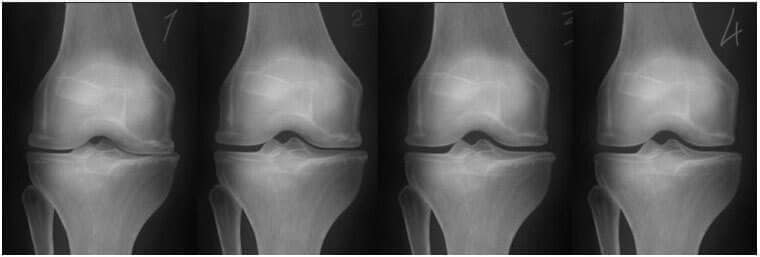

1. Nedostatak zajedničke prehrane. Tkiva niti su uništena.

2. Regeneracija tkiva zglobne hrskavice nakon dva tjedna korištenja "Osteon".

3. Regeneracija tkiva zglobne hrskavice nakon 3 tjedna korištenja "Osteon".

4. Zdrav zglob nakon završetka liječenja s Osteon.

-Donja rendgenska slika prikazuje tipičan obrazac regeneracije zgloba koljena.